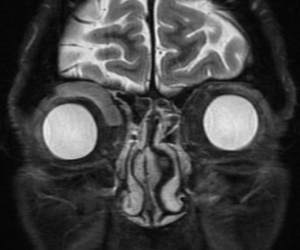

Ultrasonography of solitary fibrous tumors demonstrates low internal reflectivity with sound wave attenuation.[17] CT scan and MRI can be helpful to narrow the differential diagnosis. However, there is variability in the radiographic and MRI appearance of solitary fibrous tumors, so definitive diagnosis can only be made with histopathologic and immunohistopathologic examination. Generally speaking, solitary fibrous tumors will appear as a well-defined soft tissue mass on CT imaging that strongly enhances and may show bony remodeling if the tumor is longstanding. Significant bony changes in patients who have a history of prior tumor excision are suggestive of possible malignant degeneration.[18] Solitary fibrous tumors tend to be hypointense on T1 weighted images and iso/hypo-intense on T2 weighted images. Intralesional pseudocystic cavities are rare, but have been described,[19] and when present, may suggest malignant transformation in recurrent tumors.[20] After administration of contrast, they also tend to show a washout time intensity curve pattern. They have an apparent diffusion coefficient (ADC) value of more than 1.0 x 10-3mm2/s.[18]